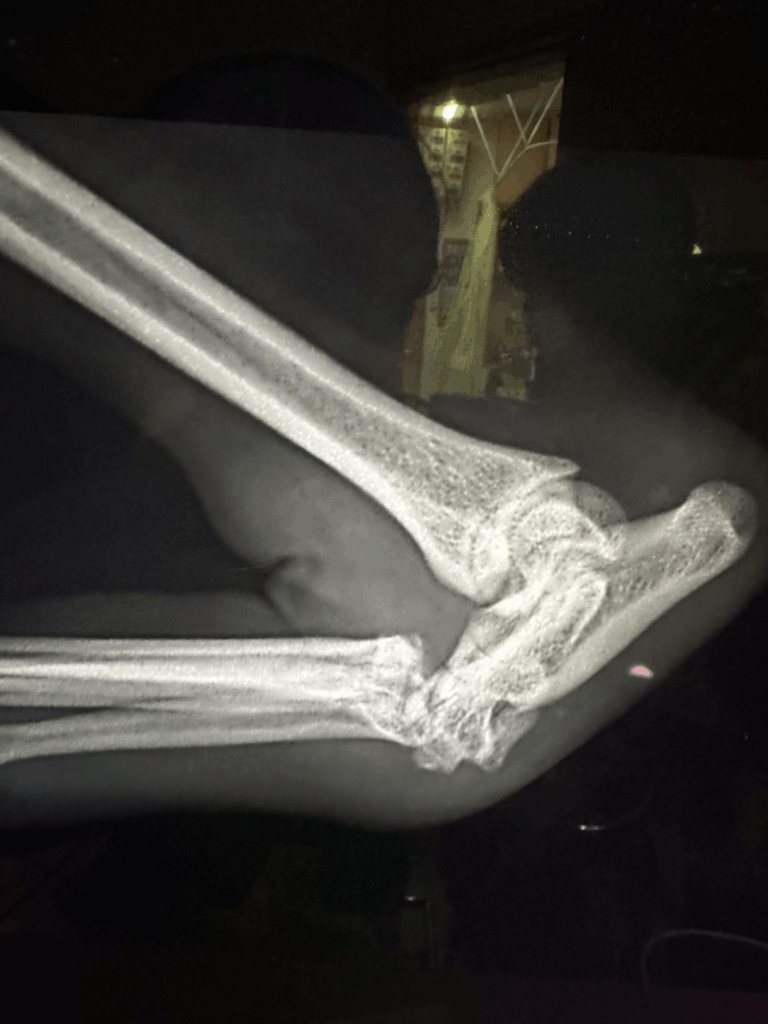

中足骨間脱臼の診断は、通常のレントゲン撮影では見逃されることも多い疾患です。

骨自体が折れていない場合、靱帯損傷や微妙な骨配列のズレを見抜くには、

整形外科に特化した知識と撮影技術、そして経験が必要です。

- 高精度レントゲンによる角度・位置の評価